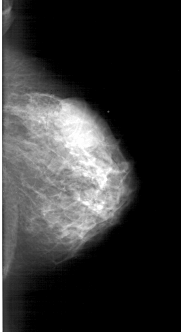

RIGHT_MLO LINES 6016 PIXELS_PER_LINE 3076 BITS_PER_PIXEL 12 RESOLUTION 43.5 NON_OVERLAY